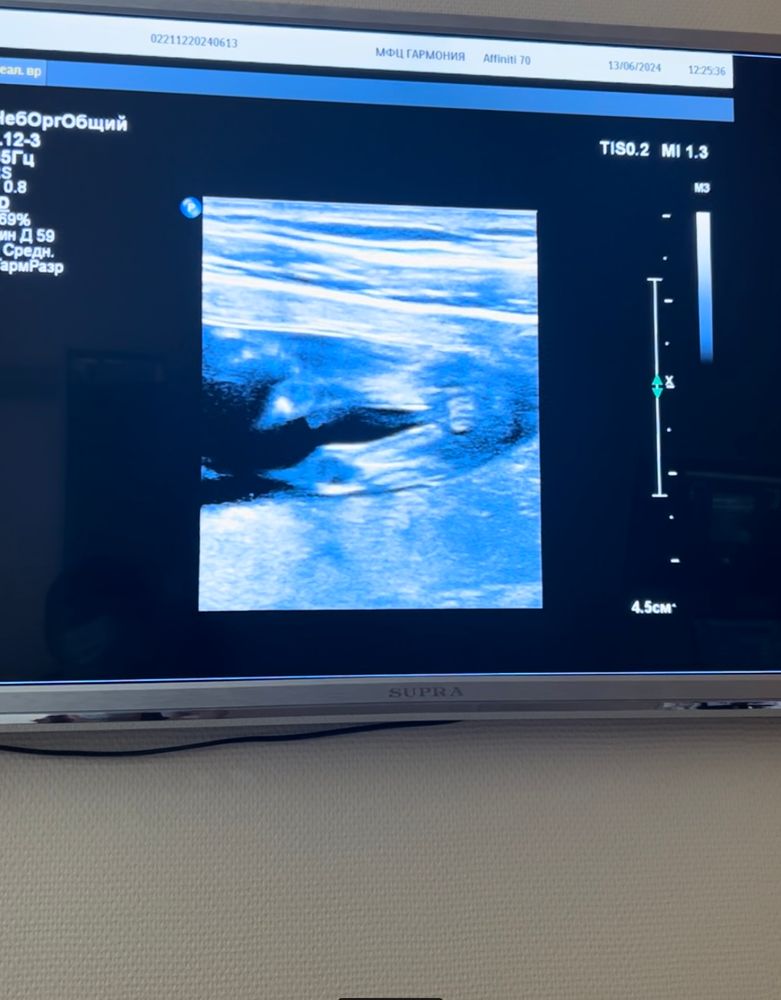

Поздно уже конечно писать, вам точно мальчика подтвердили? Просто между ног, это видимо пуповина, а остальное на таком сроке у них всё одинаково. У меня в 14 недель между ног болтался бугорок, узистка решила, что мальчик, а в итоге девочка родилась)

Насколько я знаю, именно в 12 недель смотрят по половому бугорку в профиль. Между ножек рановато. Но предположу девочку